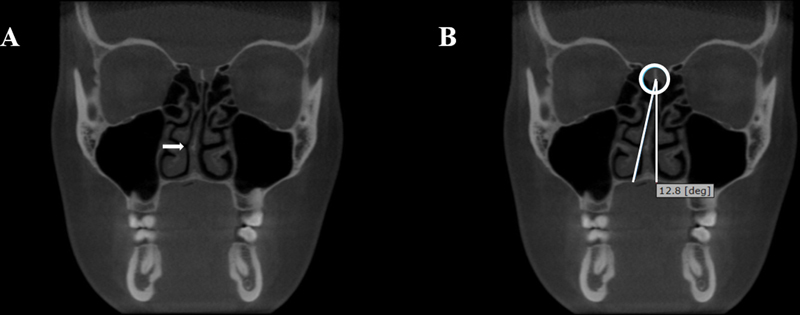

Methods: There were 297 CBCT exams assessed by two examiners who evaluated the presence of CB (> 50% pneumatization of the turbinate's height), NSD (deviation point of the nasal septum and crista galli angle >9 o ), and mucosal thickening of maxillary sinuses (mucosa around the sinus walls > 3 mm in height). The association between CB and side, NSD, mucosal thickening of the maxillary sinuses, sex, and age were evaluated by the chi-squared and Fisher's exact tests (α = 5%).

Results: A total of 208 CB was found, corresponding to 11.7% of the evaluated turbinates, being more prevalent in the middle one ( p  < 0.0001). Considering all exams, 132 (44.4%) had at least one CB. There was an association between the presence of middle left CB with NSD ( p  = 0.028). No other significant associations were found ( p  > 0.05).